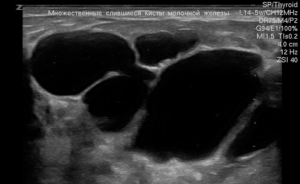

Многокамерная

В железе формируются множественные мелкие капсулы и кисты, которые постепенно сливаются. Соединений может быть множество, в каждом отсеке содержимое отличается по составу. Сложные образования часто влияют на форму грудей, делая их непропорциональными.